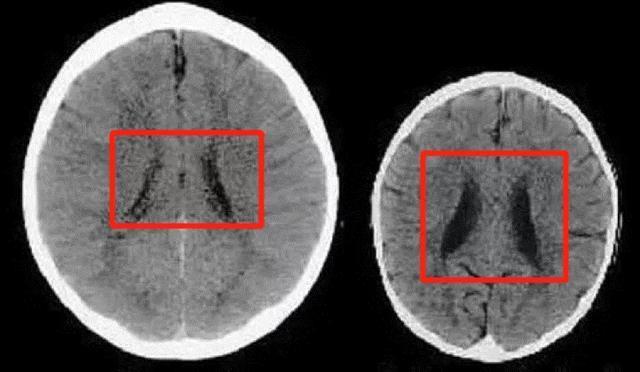

科学家曾做过一项研究,经长期跟踪扫描两个3岁孩子的大脑图形,观察他们的大脑发育差异。

其中,一个孩子的妈妈温柔善良,遇事会和孩子耐心沟通;

而另一个孩子的妈妈冷漠自私,不仅经常忽视孩子的需求,心情不好还会虐打孩子。

长期以往,同龄的孩子在不同的妈妈抚养下,大脑发育也大相径庭。如下图中,左图是第一位孩子的(被温柔以待),右图是第二位孩子的(常被打骂)。▼

图片来源网络

神经学家解释,大脑中的黑色区域越大(如右图),则意味着孩子的大脑容量越少。